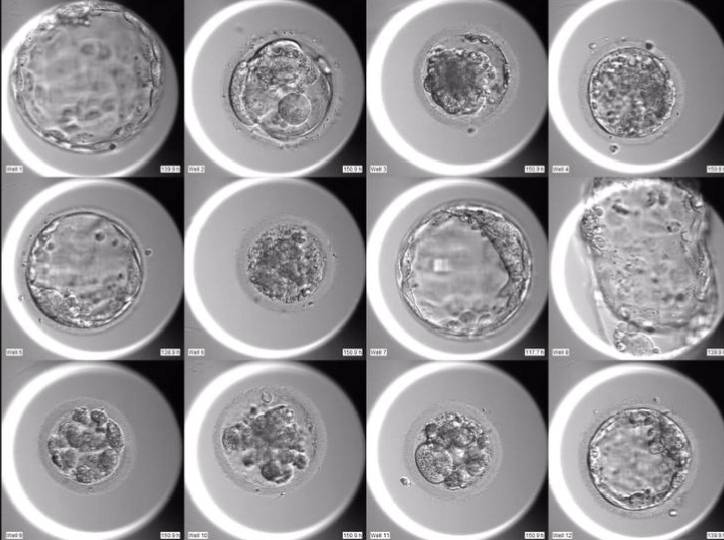

На фото недельные эмбрионы. (не мои 😁)

А сейчас можно получить фото эмбриона на 3-5-7 день его развития. 😱